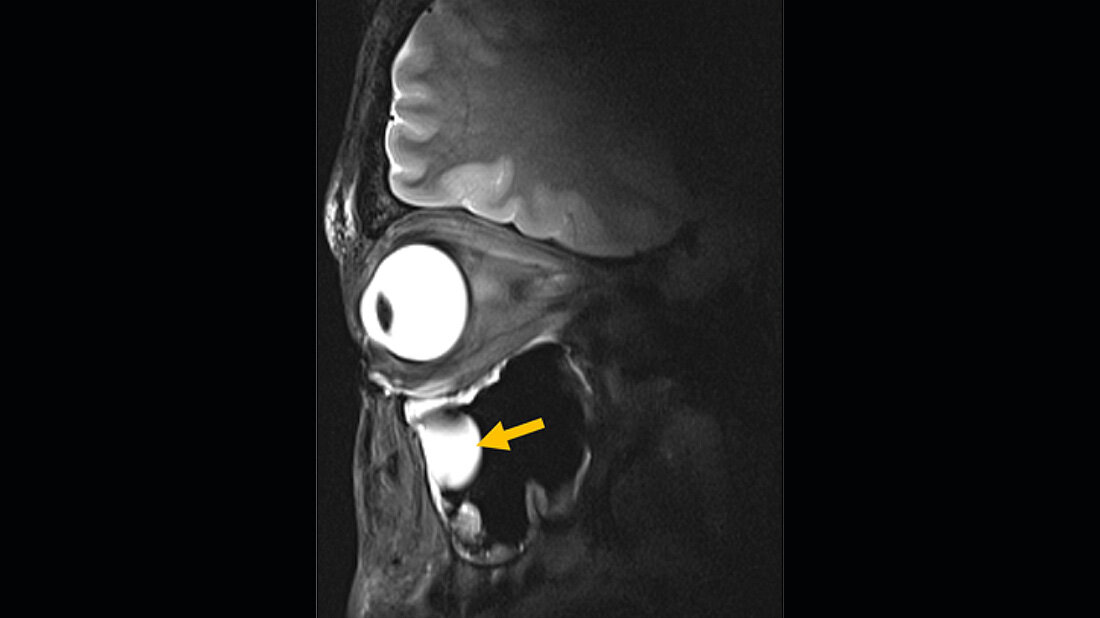

Entwickelt wurde die neue Technik mit freiwilligen Personen, die sich für die MRT-Bilder zur Verfügung stellten. Das System ist für den routinemäßigen klinischen Einsatz geeignet und in die bestehenden Infrastrukturen einbaubar. „Wir sehen eine klare Relevanz für Anwendungen in der Augenheilkunde. Die neue Technologie ermöglicht anatomisch detaillierte MRT-Bilder des Auges mit hoher räumlicher Auflösung und Weichteilkontrast“, erklärt Professor Oliver Stachs, Koautor der Publikation von der Universitätsmedizin Rostock.